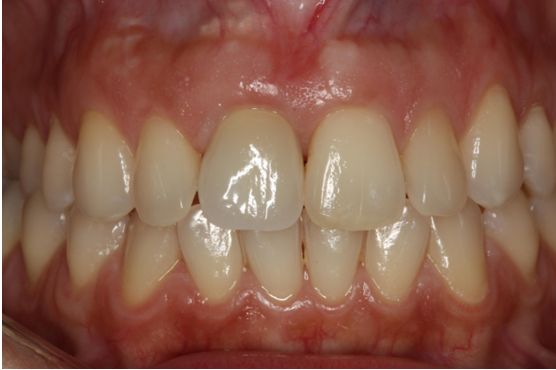

13. Θεραπεία χρόνιας περιοδοντίτιδας

Ασθενής ετών 50 προσήλθε στο ιατρείο με κύρια ενόχληση την αιμορραγία των ούλων και τη μετακίνηση των δοντιών. Οι περιοδοντικοί ιστοί ήταν ρόδινοι και εντοπισμένα ερυθροί, ενώ οι μεσοδόντιες θηλές διογκωμένες. Πολλά δόντια εμφάνιζαν υφιζήσεις, ενώ χαρακτηριστική ήταν η υπερέκφυση και απόκλιση του πλαγίου τομέα άνω αριστερά.

Παράλληλα με την περιοδοντική θεραπεία έγινε η αφαίρεση των παλαιών προσθετικών εργασιών και τοποθέτηση νέων μεταβατικών (προσωρινών) αποκαταστάσεων. Μετά τη μη χειρουργική θεραπεία παρατηρείται απουσία φλεγμονής.

ΑΡΧΙΚΗ ΚΛΙΝΙΚΗ ΕΙΚΟΝΑ

ΤΕΛΙΚΗ ΚΑΤΑΣΤΑΣΗ